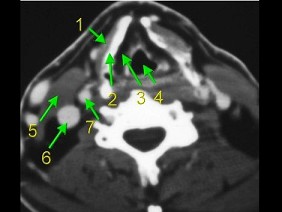

4.下面是一頸部CT圖,其中結構標志不正確的是  (    )

正確答案:D